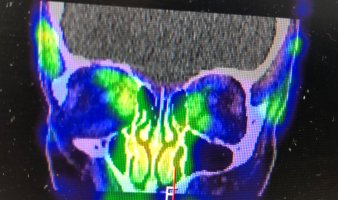

Przykładowe obrazy scyntygraficzne uzyskiwane w naszym Zakładzie Medycyny Nuklearnej: